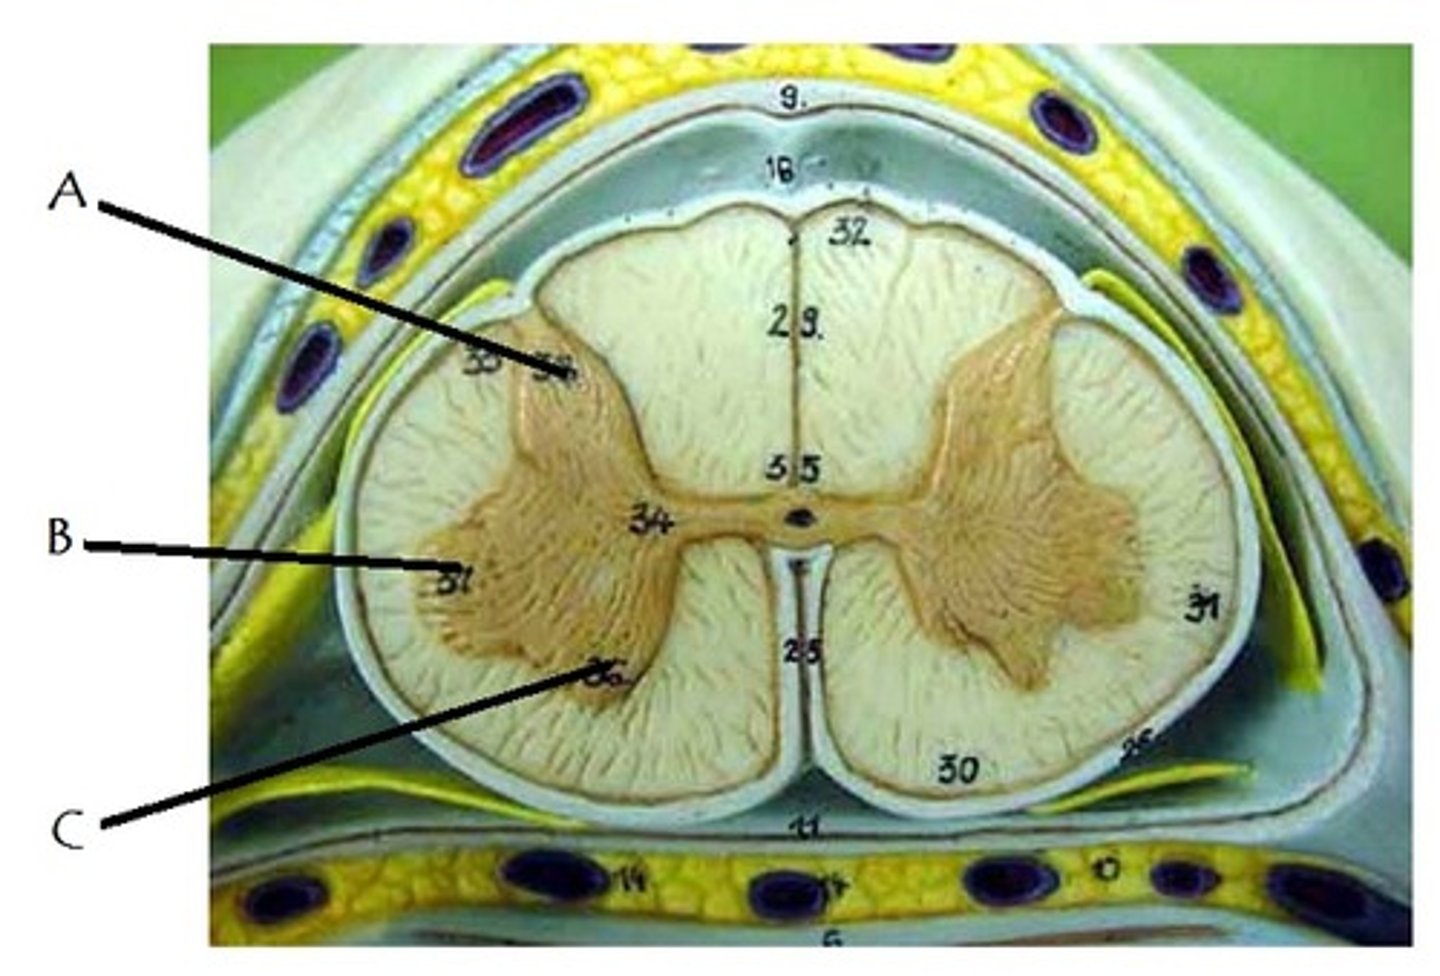

posterior gray horn

A

lateral gray horn

B

anterior gray horn

C

posterior white column

Sends information up to the brain

lateral white column

Information descends from the brain

anterior white column

Information descends from the brain (Brings info back to the spinal cord)

central canal of spinal cord

contains cerebrospinal fluid

posterior median sulcus

anterior median fissure